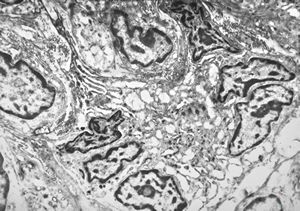

F,41y. | synovial metaplasia - capsule of implantate